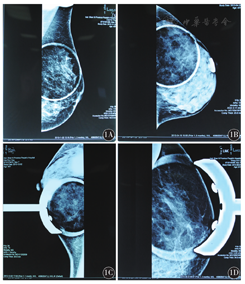

Hologic 7.5 cm局部放大压迫板进行局部点压摄影,对腺体结构紊乱或已有结节、钙化的部位标记,确定病变的位置,然后将中心的定点压迫板放在病变上方,而不影响乳腺病变周围的清晰度(图1A、图1B)。对于病灶位于乳腺的深部,紧贴胸壁或腋窝深部,常规摄影由于压迫板较大,靠深的位置触及不到,病灶不能显示,采用Hologic 7.5 cm点压迫板作局部点压,会使病灶完全显示在视野内(图1C、图1D)。在35例疑似良性或恶性病变患者中共有45处病灶,包括左乳24处,右乳21处,其中10例双侧病灶,25例单侧病灶。

1A: 7.5 cm局部放大压迫板,左乳腺斜位加压,可见外上方有一枚粗大圆形钙化,BI-RADS 2; 1B: 7.5 cm局部放大压迫板,左乳腺侧位加压,可见外上方有一枚聚集的簇状钙化,BI-RADS 3,病理结果为乳腺增生性病变;1C:7.5 cm点压迫板,经左乳腺侧位加压,可见内下方几颗集中的细小钙化点,BI-RADS 3,病理结果为纤维腺瘤;1D: 7.5 cm点压迫板,经左乳腺正位加压,可见外侧上方多发簇状细小钙化点,BI-RADS 4c,病理结果为乳头状导管原位癌